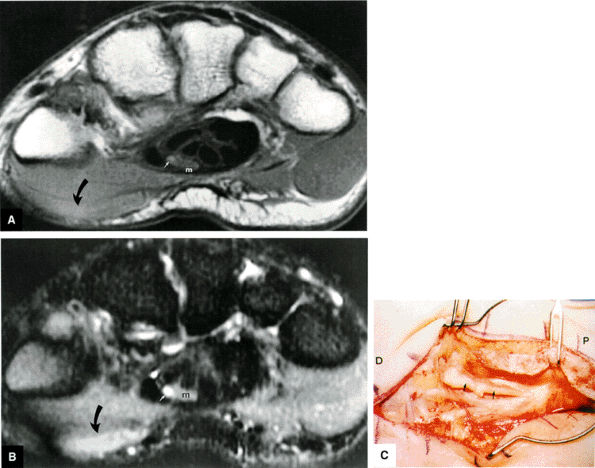

-

Pain and numbness or tingling in the median nerve distribution with increased nocturnal pain and/or burning (can be classified as mild, moderate, or severe based on electrodiagnostic data or by severity of clinical symptoms)

Involvement of the thumb, index, middle fingers, and radial half of the ring finger is most common.

Sensory findings ranging from minimal hypesthesia to complete anesthesia

Muscle atrophy and loss of function are usually late findings, although abductor pollicis brevis involvement and opponens weakness may be seen earlier (opponens atrophy is a late finding).

Positive clinical tests for nerve entrapment: